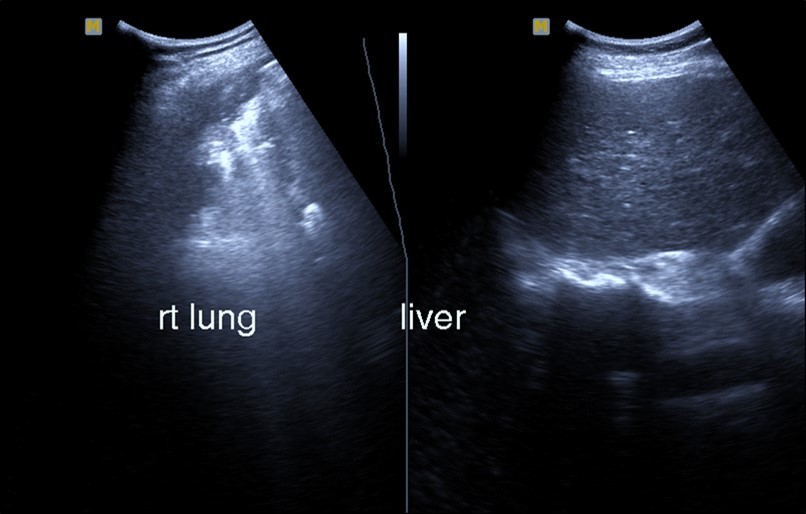

Abdominal ultrasound may revealed any of the followings:-Mild hepatomegaly with echogenic parenchyma and ascites in cases with hepatic impairment (Figure 4, Figure 5) ,thick walls of gall bladder with mildly dilated Common bile duct suggesting of biliary stasis and cholecystitis (Figure 6) .Abnormal renal echogenicity (Figure 7), suprarenal gland enlargements with heterogeneous texture ,splenic wedge shape area of hypoechogenicity ,thickened walls of bowel mainly the rectosigmoid region ,dilated bowel loops with free peritoneal fluid, and gases in the bowel wall with mesenteric and portal vein gases suggesting of bowel wall infarction13.

Figure 5.Real time ultrasound showing mild hepatomegaly (li), ascites and thickened gall bladder wall(gb).

Figure 6.Real time ultrasound showing free ascites (asc) in patient with Covid-19.